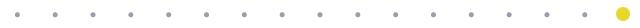

经匡正达主任诊治后,发现患者有先天性腰椎骶化,极易误诊,如果间隙做错了,那后果不堪设想。又考虑到患者要干农活,如果单纯椎管减压,有术后不稳的可能,而且患者长期生理性脊柱侧弯,综合考虑,最终决定为患者实施腰椎管减压的同时,进行椎间植骨融合钉棒内固定术。

腰椎正位平片-术前